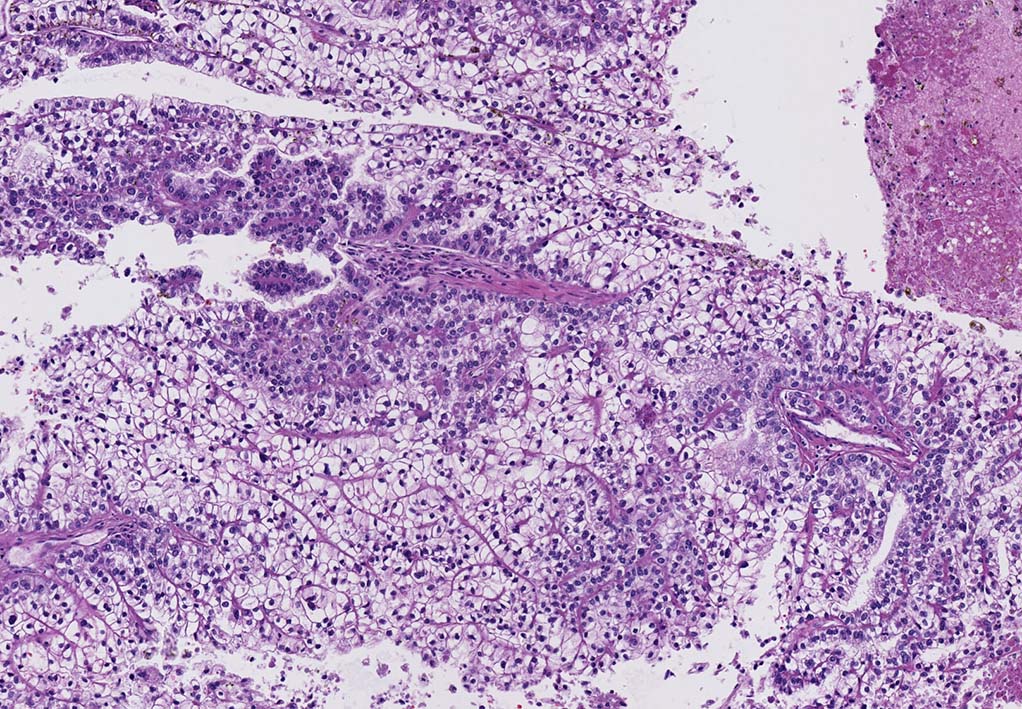

microscopicには線維血管性間質をもち乳頭状または管状乳頭状に細胞が増殖する. 間質にはpsamomaや泡沫細胞の集簇, 硝子化がしばしば認められる.

細胞異型度により1型; 小型立方状, 細胞質は乏しく淡明または好塩基性, 核偽重層はない.核異型はめだたない.(3分類法/FuhrmanでGrade1-2),

2型; 細胞は円柱状で, 不規則な偽重層を呈する. 細胞質は豊で好酸性, 核異型がめだつ(Grade3相当)に分類されている.